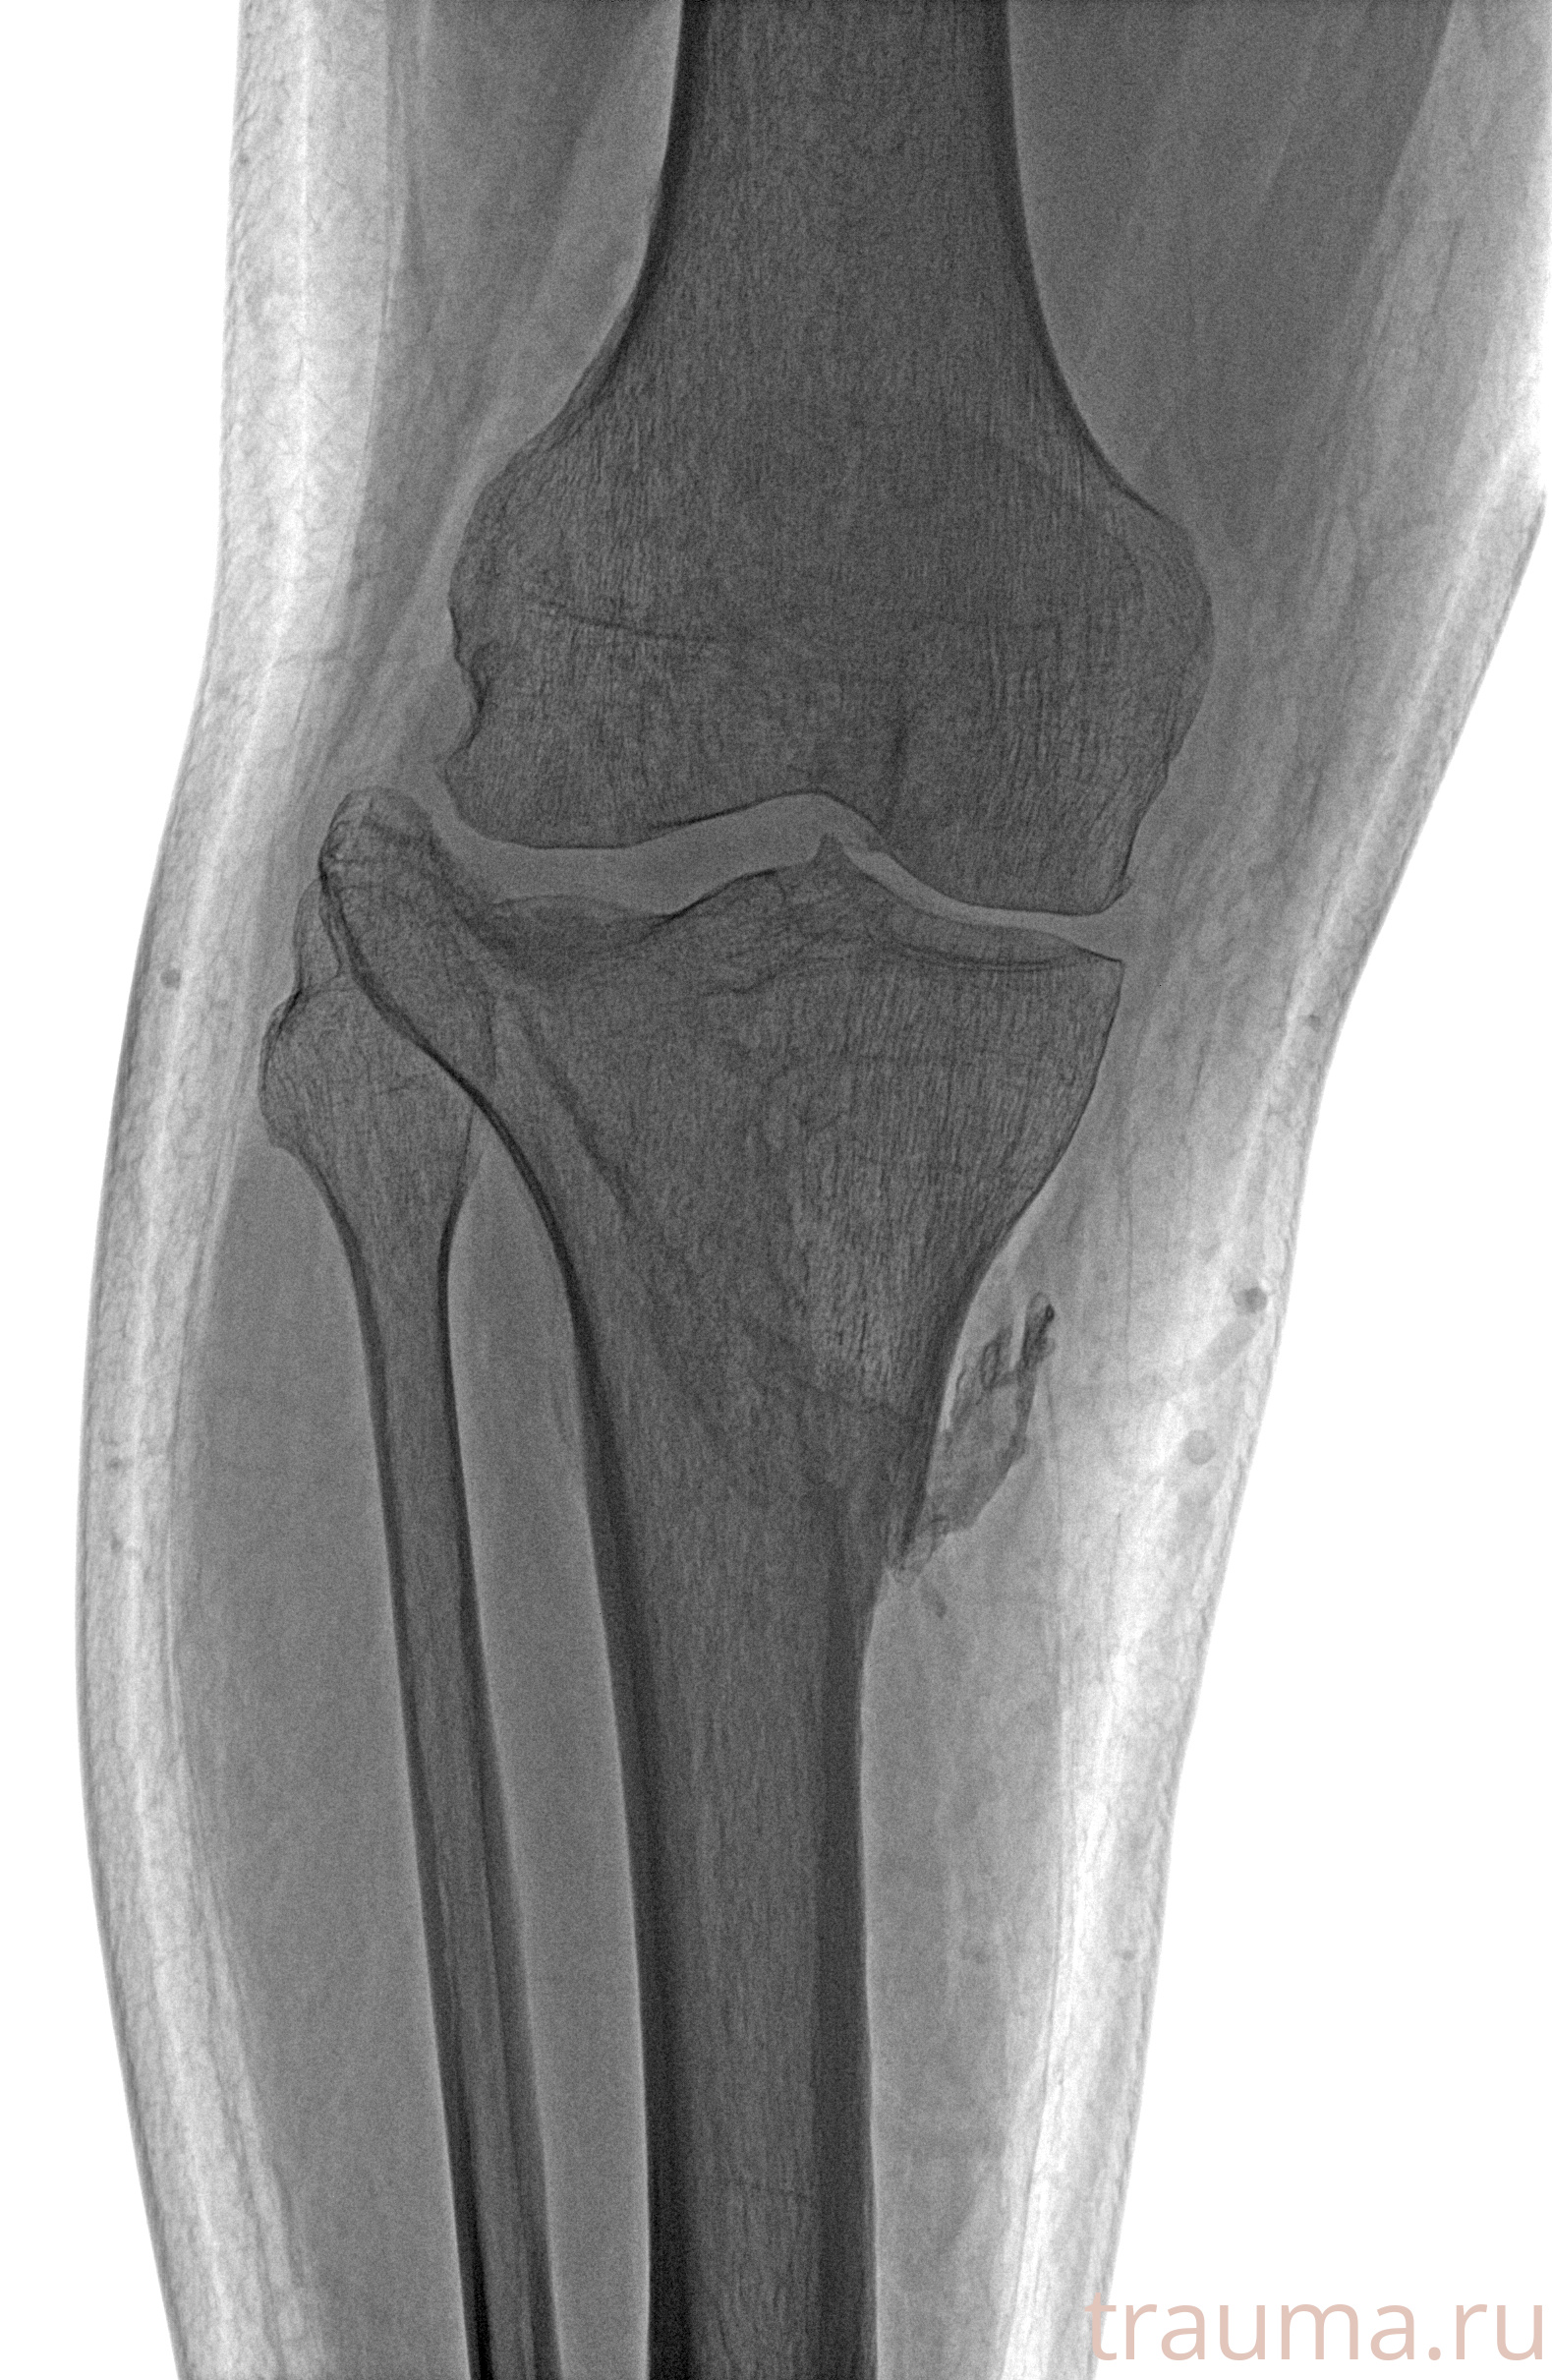

Рентгенограммы

Рентген на дому: по вашему адресу приезжает врач-рентгенолог, травматолог-ортопед с мобильным рентгеновским аппаратом, проводит диагностику травмы или заболевания, делает необходимые рентгенограммы, дает рекомендации по дальнейшему лечению. Получить качественные снимки в домашних условиях возможно благодаря уникальной методике, разработанной МосРентген Центром для института  Склифосовского